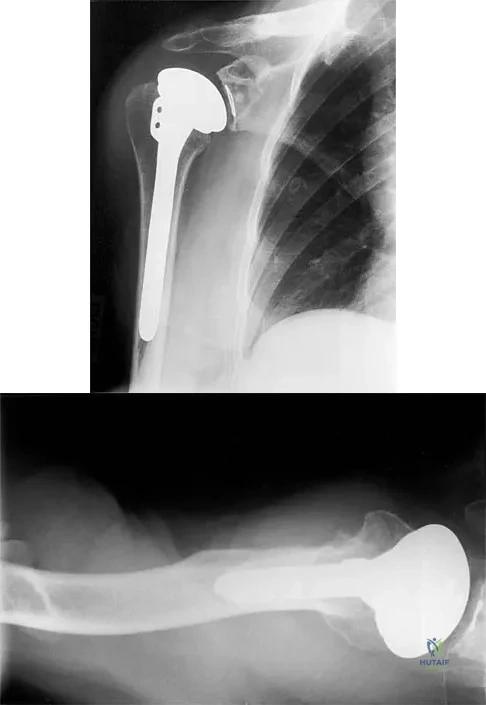

Question 59

A 54-year-old man undergoes total shoulder arthroplasty for osteoarthritis. Despite compliance with an early passive range-of-motion exercise program, he does not regain more than 90 degrees of elevation, 10 degrees of external rotation, and has internal rotation to the fifth lumbar vertebra. At 6 months, his motion fails to improve. Radiographs are shown in Figures 18a and 18b. What is the best course of action?

Explanation